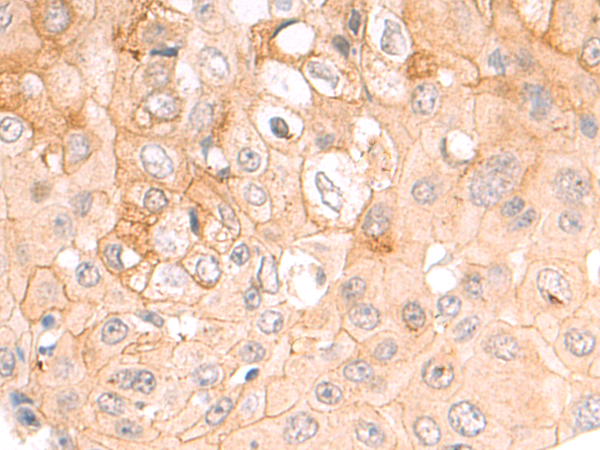

分类: 科研抗体货号: P08789别名: CEDNIK; SNAP-29应用: IHC反应种属: Human, Mouse, Rat